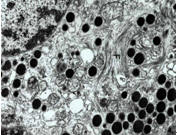

2.電鏡表現為毛細血管明顯擴張,腔內充滿大量大小不等及電子密度不一的顆粒,這些顆粒可呈條紋狀排列,類似指紋結構。也有腔內填充物質為大小不等的空泡結構,常呈簇狀或層狀排列。腔內紅細胞及內皮細胞被擠壓於脂蛋白血栓樣物質與毛細血管壁之間。系膜區早期僅表現為輕度增生,病變進展時,系膜區明顯增寬,系膜細胞及系膜基質增生,有時可出現系膜插入、系膜溶解等改變。腎小球基底膜未見增厚、緻密物沉積。